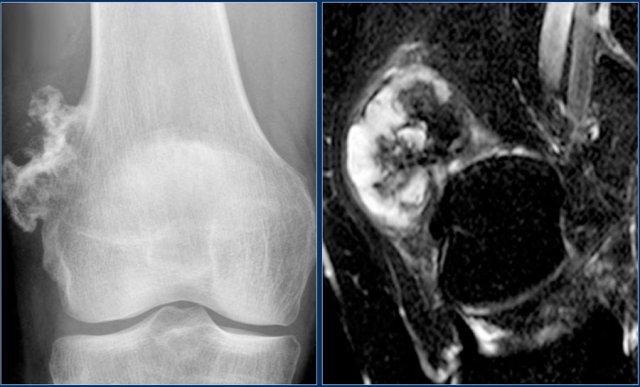

Hình ảnh cho thấy một tổn thương vôi hóa ở đầu gần xương chày mà không có đặc điểm đáng ngờ.

Đây rất có thể là một u sụn nội xương (enchondroma).

Có những đặc điểm khác ủng hộ chẩn đoán sarcoma sụn độ thấp như xạ hình xương dương tính và hình ảnh xói mòn nội màng xương trên MRI (không hiển thị).

Sarcoma sụn đã được chẩn đoán qua sinh thiết.